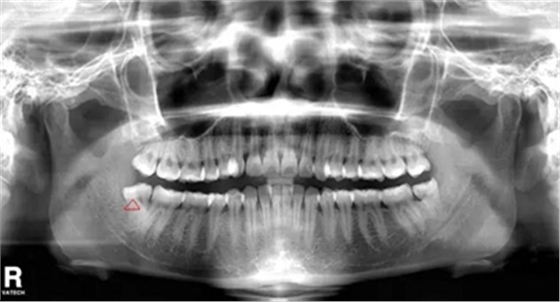

智齒遠(yuǎn)中阻生(遠(yuǎn)離鄰牙方向長)反復(fù)炎癥感染

5.反復(fù)發(fā)炎的智齒